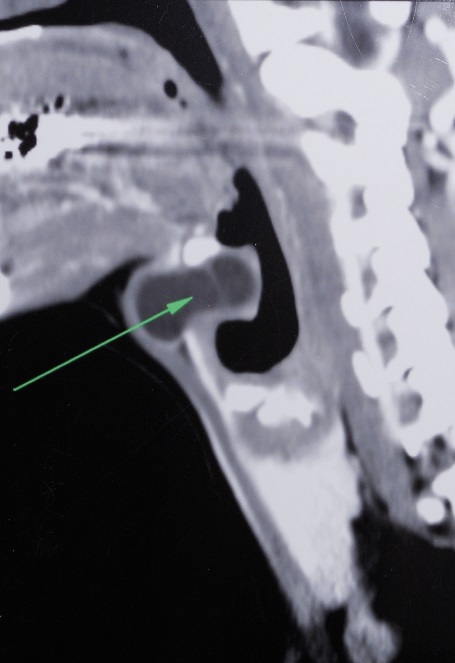

Thyroglossal duct cyst (TDC) is the most common congenital neck mass, approximately 7% of the Population has a TDC. It results from incomplete resorption of the thyroglossal duct during embryogenesis. A 31-year-old male patient presented with a painful left paramedian neck swelling for two months. Physical examination revealed a cystic mobile swelling; the lesion disappeared on hyperextension of the neck and reappeared on lateral rotation to the left side. Cervical CT scann revealed a bilobular cystic mass on the prominentia thyroidea, and extending deeply into the preepiglottic region, turning medially from the upper border of the thyroid cartilage (Figure 1). Surgery revealed a cystic lesion with intralaryngeal extension through a defect in the thyrohyoid membrane. In the last step of the surgery, as described in the Sistrunk procedure, the central portion of the hyoid bone was included in the specimen. The tract was followed to the tongue base and then cut after ligation. Histopathology confirmed the diagnosis of an inflamed TDC. During the 6-month postoperative follow-up of the patient, no finding consistent with recurrence was detected in the surgical site. TDC may be located at the level of the hyoid (15-50%), the suprahyoid (20-25%), or the infrahyoid (25-65%). The intralaryngeal location of a thyroglossal duct cyst is rare and only a few cases have been reported, which makes this case interesting. TDC can extend from the thyroid cartilage. It can push or destroy the thyrohyoid membrane and then progress to the laryngeal ventricle, which causes it to be confused with saccular cyst or laryngocele. Airway obstruction due to intralryngeal thyroglossal duct cyst can cause the disease to show a fatal course. Evaluation of laryngeal structures with preoperative endoscopic and radiological techniques is an important step that can help the diagnosis. Sistrunk procedure should be administered for such cases.